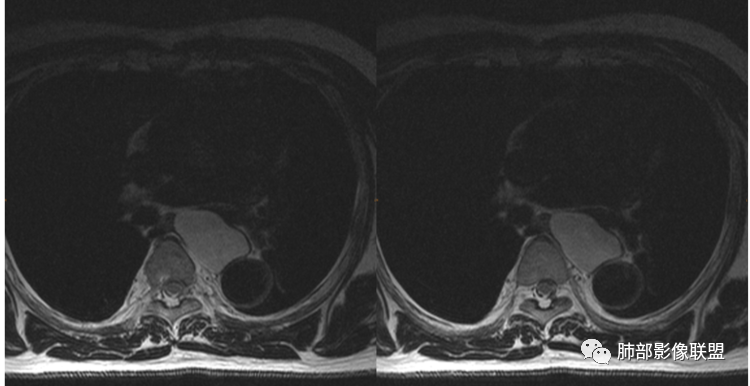

男性,43岁,体检发现后纵隔占位,边缘光整,CT示密度均匀,周围组织受压移位,无钙化囊变及脂肪组织,增强未见明显强化。MRI:T1示肿块信号较肌肉高,T2不均匀高信号。考虑为良性病变,第一是神经节细胞瘤,其次是支气管源性囊肿。

中年男性,无症状,后纵隔肿块,长径大矢状位于横径,质地偏软,塑形,等t1稍长t2,比较均质,增强轻微强化,与脊柱,主动脉,食管脂肪间隙存在,部分层面与脊柱相贴,骨质无改变,周围无肿大淋巴结,考虑神经源性肿瘤,节细胞神经瘤可能大,鉴别心包斜窦,淋巴瘤,淋巴管囊肿。

后纵隔占位,椭圆形,边缘不规则,CT低密度,MRI长稍长T1稍长T2信号,增强扫描未见强化,支气管受压。囊性病变,考虑支气管囊肿(常见,T1WI稍低“比水高”T2WI稍高,可能与其内含有粘液或蛋白有关);鉴别淋巴管囊肿(更软塑性性更大,接近纯水MRI信号长T1长T2,受周围挤压更明显,变形。);神经节细胞瘤瘤(增强可有轻度渐进性强化,也可不强化,关键是不常见),还有就是神经源性囊肿与肠源性性囊肿。

后纵隔占位;食道向右侧推移,病变质软,CT平扫密度均匀,边缘清晰光整,MRI 稍长T1,长T2高,脂肪抑制高信号。考虑纵隔良性囊性占位。先考虑支气管囊肿。其它类囊肿待除外。

左后纵隔食管旁占位,边界清晰,增强目测未见明显强化,稍长T1稍长T2信号,信号尚均匀,病灶较软,和食管紧贴,定性良性,首先考虑前肠囊肿,以支气管囊肿可能性大,鉴别节细胞瘤。

定位,后纵隔囊性占位,边界清楚,内部密度均匀,张力高,囊壁均匀,周围结构受压,增强后无强化。MRI:长T2信号。考虑良性囊性病变,支气管囊肿、淋巴管囊肿。